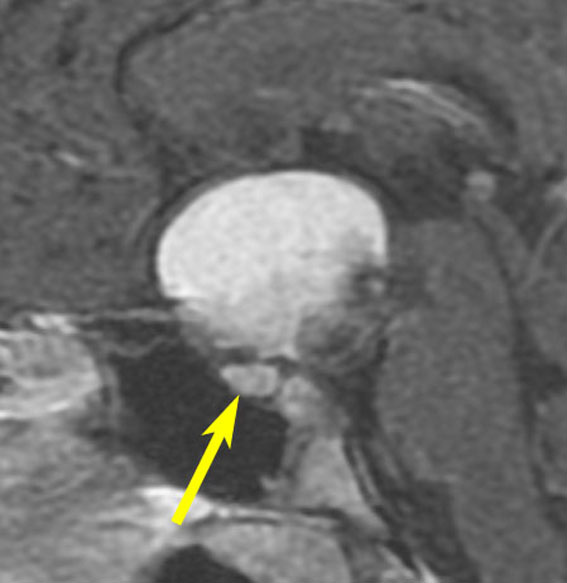

7歳の子が視力障害で発症しました。両耳側半盲という症状です。典型的な鞍隔膜下頭蓋咽頭腫です。ガドリニウム造影剤を入れないMRIでみえる,黄色い矢印の先の白い高信号は抗利尿ホルモンです。ですから下垂体機能もまだ残っていて,尿崩症はありません。視力障害が戻らないことがあるのでなるべく早く,経鼻的な手術で摘出した方がいいものです,簡単 o(^-^)o